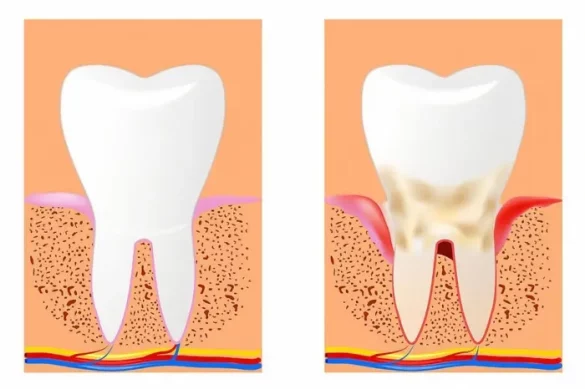

The alveolar bone is the a part of your jaws that holds your tooth in place. It now no longer best offers important guide however additionally shapes your jawline and determines factors of your facial appearance. Unlike what many would possibly think, bone tissue isn’t always static. It is continuously converting relying on inner and outside conditions. This dynamic nature permits for useful adjustments all through orthodontic treatment, however it additionally method that the bone can become worse in destructive environments.

The maximum not unusualplace reasons of alveolar bone loss are periodontal (gum) ailment and enamel loss.

When plaque builds up below the gum line, it results in irritation and infection. Over time, this undermines the systems that guide your tooth, inclusive of the alveolar bone. Without treatment, bone density drops, that may reason unfastened tooth and can even cause enamel loss.

Your jawbone desires the stimulation furnished with the aid of using herbal tooth. When a enamel is lost, the bone below that region not gets vital stimulation. As a result, it starts offevolved to become worse. People who lose more than one tooth are at excessive chance for big bone loss, that may cause substantive adjustments in facial structure, frequently making someone appearance older.